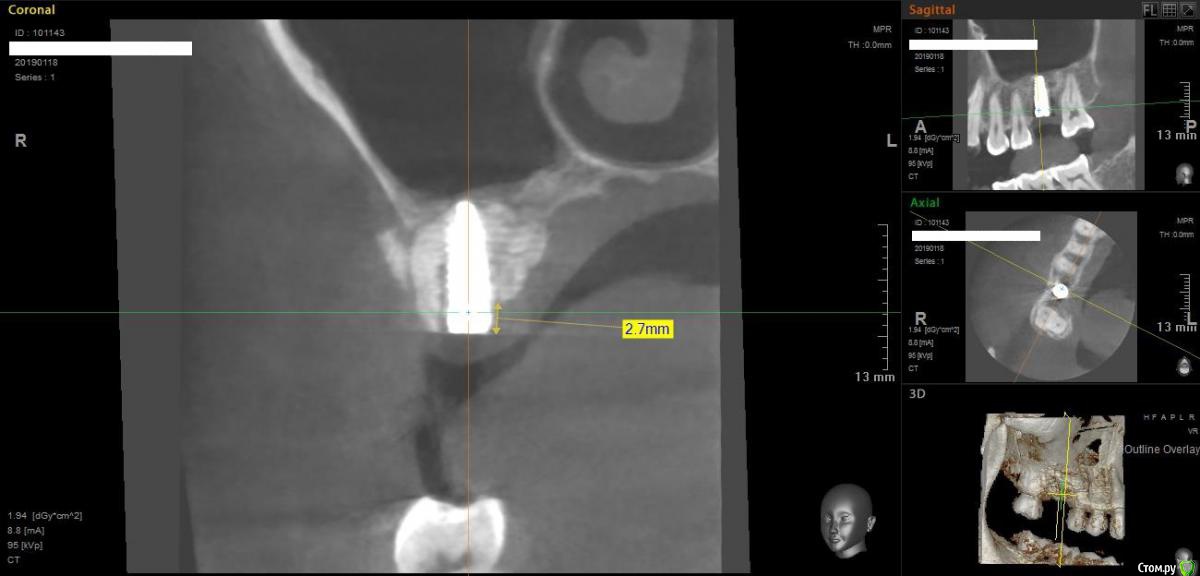

Norton Опубликовано 14 апреля, 2019 Поделиться Опубликовано 14 апреля, 2019 (изменено) Доброго времени суток уважаемые коллеги. Ко мне обратилась пациентка с установленным импл. в области верхней 6 (XIVE 3.8 / 11 мм). Сейчас назревает вопрос нужна ли мягкотканная пластика или нет? Cмутило то, что несколько коллег в моем городе порекомендовали сделать. Изменено 14 апреля, 2019 пользователем Norton Ссылка на комментарий

Дмитрий М Опубликовано 18 апреля, 2019 Поделиться Опубликовано 18 апреля, 2019 (изменено) отлом вестибулярной или миграция графта?похоже свободный фрагмент, пальпируется нет? Изменено 18 апреля, 2019 пользователем Дмитрий М Ссылка на комментарий

Magadalina Опубликовано 19 апреля, 2019 Поделиться Опубликовано 19 апреля, 2019 Похоже на выход графта сразу после синус- лифтинга через окно. Это никакого значения не имеет Ссылка на комментарий

Norton Опубликовано 20 апреля, 2019 Автор Поделиться Опубликовано 20 апреля, 2019 что это.jpg отлом вестибулярной или миграция графта?похоже свободный фрагмент, пальпируется нет?Нет, я на это тоже обратил внимание Ссылка на комментарий